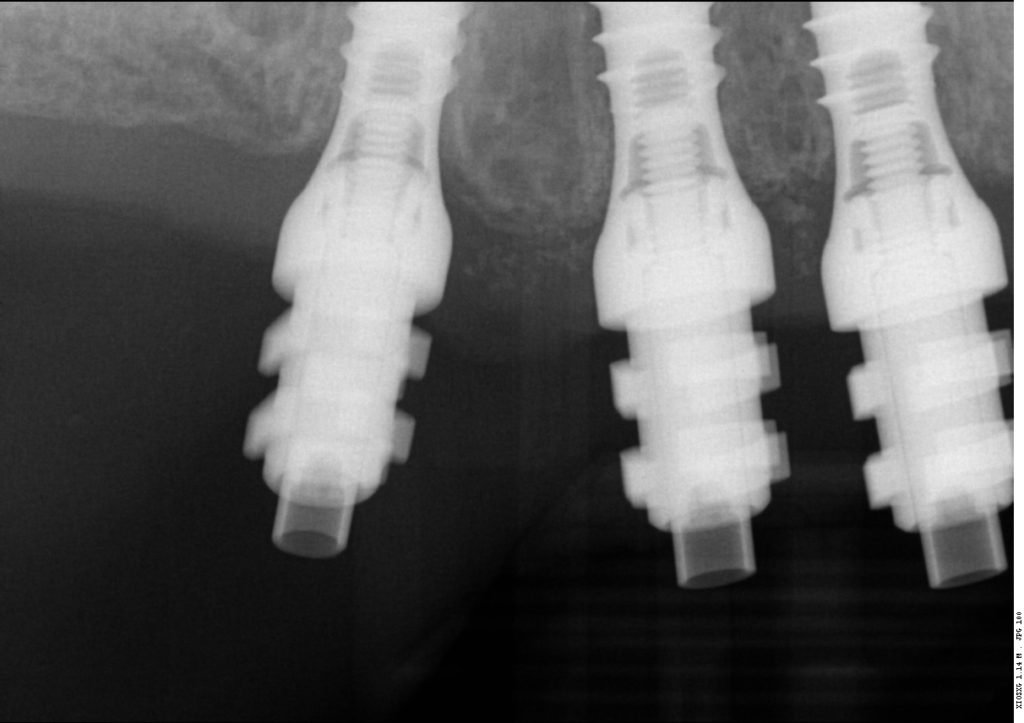

Multiple intra-operative radiographs were taken using depth gauges of gradually increasing diameter to ensure ideal positioning, particularly near vital structures such as the maxillary sinus. Following three months healing, definitive impressions were taken. Radiographs were taken to confirm complete seating of the impression copings prior to splinting of the impression copings and then impression taking.

Records stage: due to the fact that all records were gained by the adjustment and confirmation of the provisional removable complete maxillary denture, records were quite straightforward. The complete denture was copied, flanges were removed, and the resulting guide was then seated over the existing tissue level healing abutments. A PMMA bridge with plastic inserts was constructed digitally in the laboratory and sent for final confirmation prior to construction of the definitive porcelain-fused-to-zirconia bridge. The definitive bridge was inserted and radiographs were taken to confirm full seating and correct emergence profile. Once passivity of fit was confirmed, abutments crews were torque to 35 Ncm, and the access cavities were restored with PTFe tape and composite resin. The occlusion was adjusted to ensure guiding services were smooth, concave and gradually increasing pre-truce in steepness, and smooth shared group function in lateral excursion.